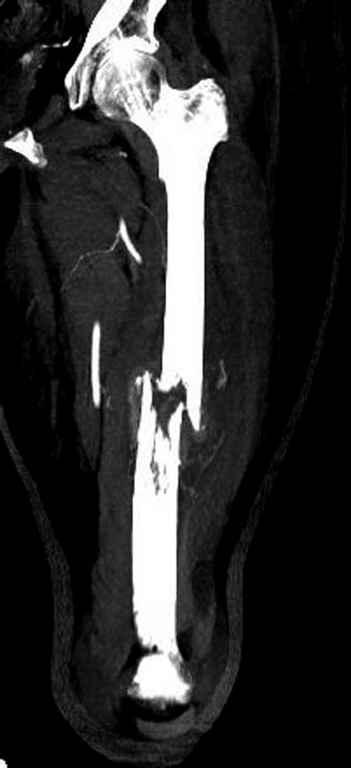

Здесь случай 66 летней пациентки со спонтанными болями в левой нижней конечности, обратилась в приемное, сделаны снимки бедра и КТ.

Патологический перелом бедра, конечность на вытяжении.

Со слов, больная ничем не болела, только последние 3 месяцев чувствовала боли в бедренной области. КТ брюшной полости подтвердил увеличенную правую почку. (5-6)

Для предупреждения кровотечения во время рассверливания, за день до операции провели эмболизацию сосудов питающий метастаз. http://radiology.rsnajnls.org/cgi/reprint/150/3/673.pdf (7-11, 12-15-16)

С минимальным рассверливанием и ретроградным методом провели остеосинтез бедра 12 мм гвоздем. (17-20)